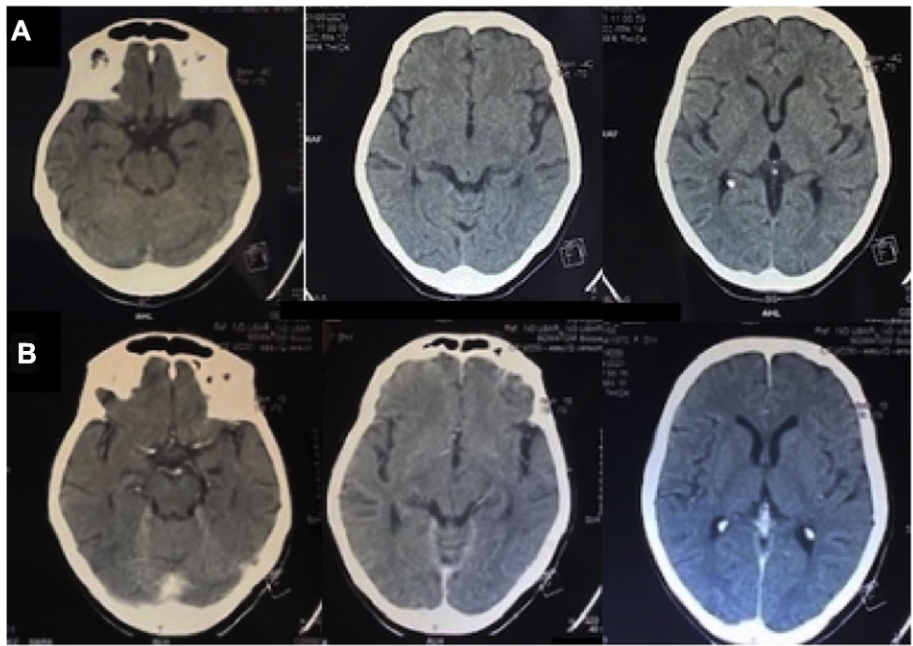

• • 一名29岁的男性在一次车祸中遭受了孤立的头部创伤。复苏后GCS评分为7分,双侧瞳孔反射存在。首次头颅CT显示广泛的颅顶骨折,外伤性SAH,硬膜下血肿和双额叶挫伤,无明显占位效应和基底池开放(图6a)。CTA未发现脑动脉或静脉窦损伤。入住ICU,置入硬膜下装置监测ICP。24h后,患者病情恶化,出现IH,对镇静、神经肌肉阻滞、高渗盐水或巴比妥类药物反应欠佳。头颅CT显示额叶挫裂伤无明显增大,无占位效应,环池未闭(图6b)。置入腰大池外引流管后,ICP即刻得到控制。随着时间的推移,其他治疗方法也慢慢撤退。患者预后良好,6个月的GOSE评分为7分。

腰穿有什么用病例系列报道——使用控制性腰穿引流治疗基底池未闭的难治性颅内高压_https://www.jmylbn.com_新闻资讯_第7张

图6 案例9。a首诊头颅CT示广泛颅顶骨折、外伤性蛛网膜下腔出血、硬膜下血肿、双额叶脑挫裂伤,无明显占位效应,基底池显示良好;b 24h后复查头颅CT示额叶脑挫裂伤无明显增大,无占位效应,环池显示良好。